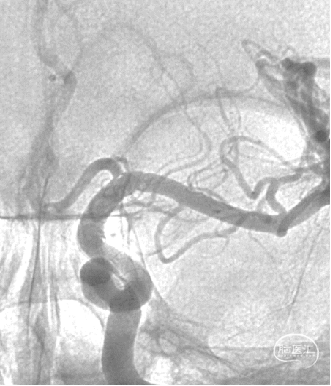

现病史:患者因头痛17天,外院行头颅CTA提示:左侧颈内动脉交通段动脉瘤,动脉瘤大小约5.3×5.4mm,形态不规则,左侧大脑前动脉A1段瘤样凸起。

可见一小泡自动脉瘤瘤体上发出

瘤体最大径6.92mm

远端血管直径:3.28mm

近端血管直径:3.98mm

同侧A1可见一小瘤突起